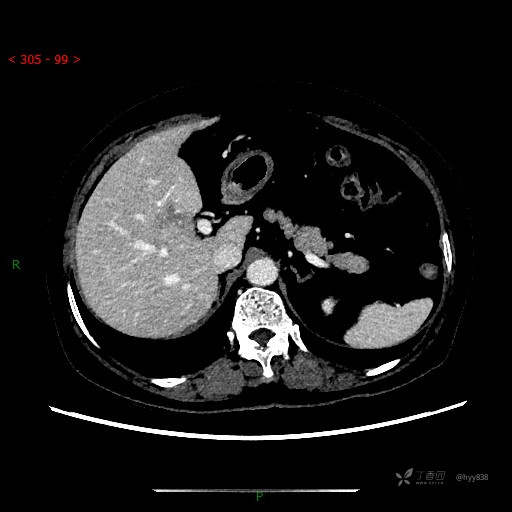

增强动脉期